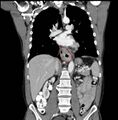

Additional testing is needed to assess how much the cancer has spread (see § Staging, below). Computed tomography (CT) of the chest, abdomen and pelvis can evaluate whether the cancer has spread to adjacent tissues or distant organs (especially liver and lymph nodes). The sensitivity of a CT scan is limited by its ability to detect masses (e.g. enlarged lymph nodes or involved organs) generally larger than 1 cm.[43][44] Positron emission tomography is also used to estimate the extent of the disease and is regarded as more precise than CT alone.[45] PET/MR as a novel modality has shown promising results in preoperative staging with fair feasibility and good correlation in comparison to PET/CT. It can enhance tissue differentiation with lowering the radiation dose to the patient.[46] Esophageal endoscopic ultrasound can provide staging information regarding the level of tumor invasion, and possible spread to regional lymph nodes.

Contrast CT scan showing an esophageal tumor (coronal view)